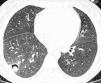

Dentro de las pruebas no invasivas, la tomografía computarizada de alta resolución (TCAR) se ha convertido en un elemento indispensable para establecer un diagnóstico precoz de IFI42-44. Ésta presenta una cinética característica a lo largo del proceso. En el momento del diagnóstico, fase precoz de la infección, el "signo del halo" es el hallazgo más frecuente y se corresponde con una zona de edema o hemorragia de baja atenuación alrededor de una masa o nódulo (figs. 2 y 3). Más adelante, las lesiones se cavitan, aparece aire en su interior y toman aspecto de semiluna42,43.

Figura 2. Signo del halo en aspergilosis invasora.

Figura 3. Signo de la semiluna.